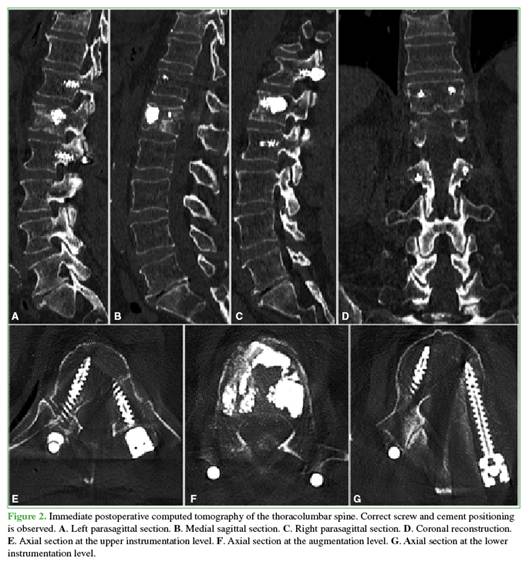

Preoperative images

Figure 1 shows preoperative magnetic resonance imaging of the lumbar spine, including midsagittal T1-, T2-, and STIR-weighted sequences, as well as an axial slice at the level of the L1 vertebral body. A lesion is observed compromising the vertebral body structure and predominantly involving the anterior column at the L1–L2 segment, without spinal canal involvement. The lesion appears hypointense on T1- and T2-weighted sequences and hyperintense on STIR images.